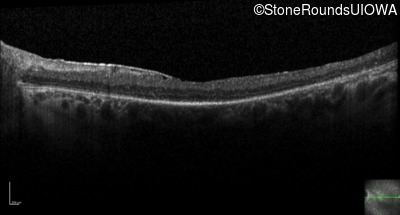

Optical Coherence Tomography - Right - 20/80 +1

Exemplar / OCT Stack

OCT Stack